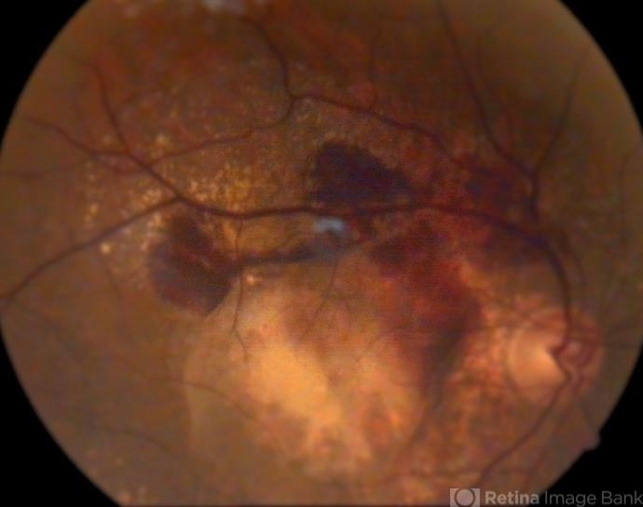

Symptoms and Treatment for AgeRelated Macular Degeneration